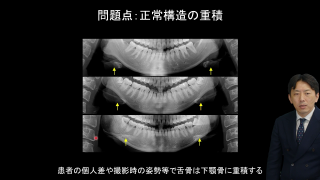

歯科用CTは昨年度までに30,000台近く普及したと推計されており、多くの歯科医師が三次元画像を用いて簡単に診断する時代が到来しています。歯科用CTは、これまでの画像検査と何が異なるのか?そのメリットをどう活かすべきなのか?何に注意して画像を見るべきか?を中心に、歯科用CT画像の特徴や診断における注意点などを解説します。